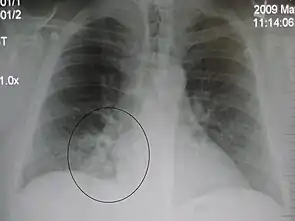

| A chest X-ray showing a very prominent wedge-shape bacterial pneumonia in the right lung | |

Right upper lobe pneumonia as marked by the circle.